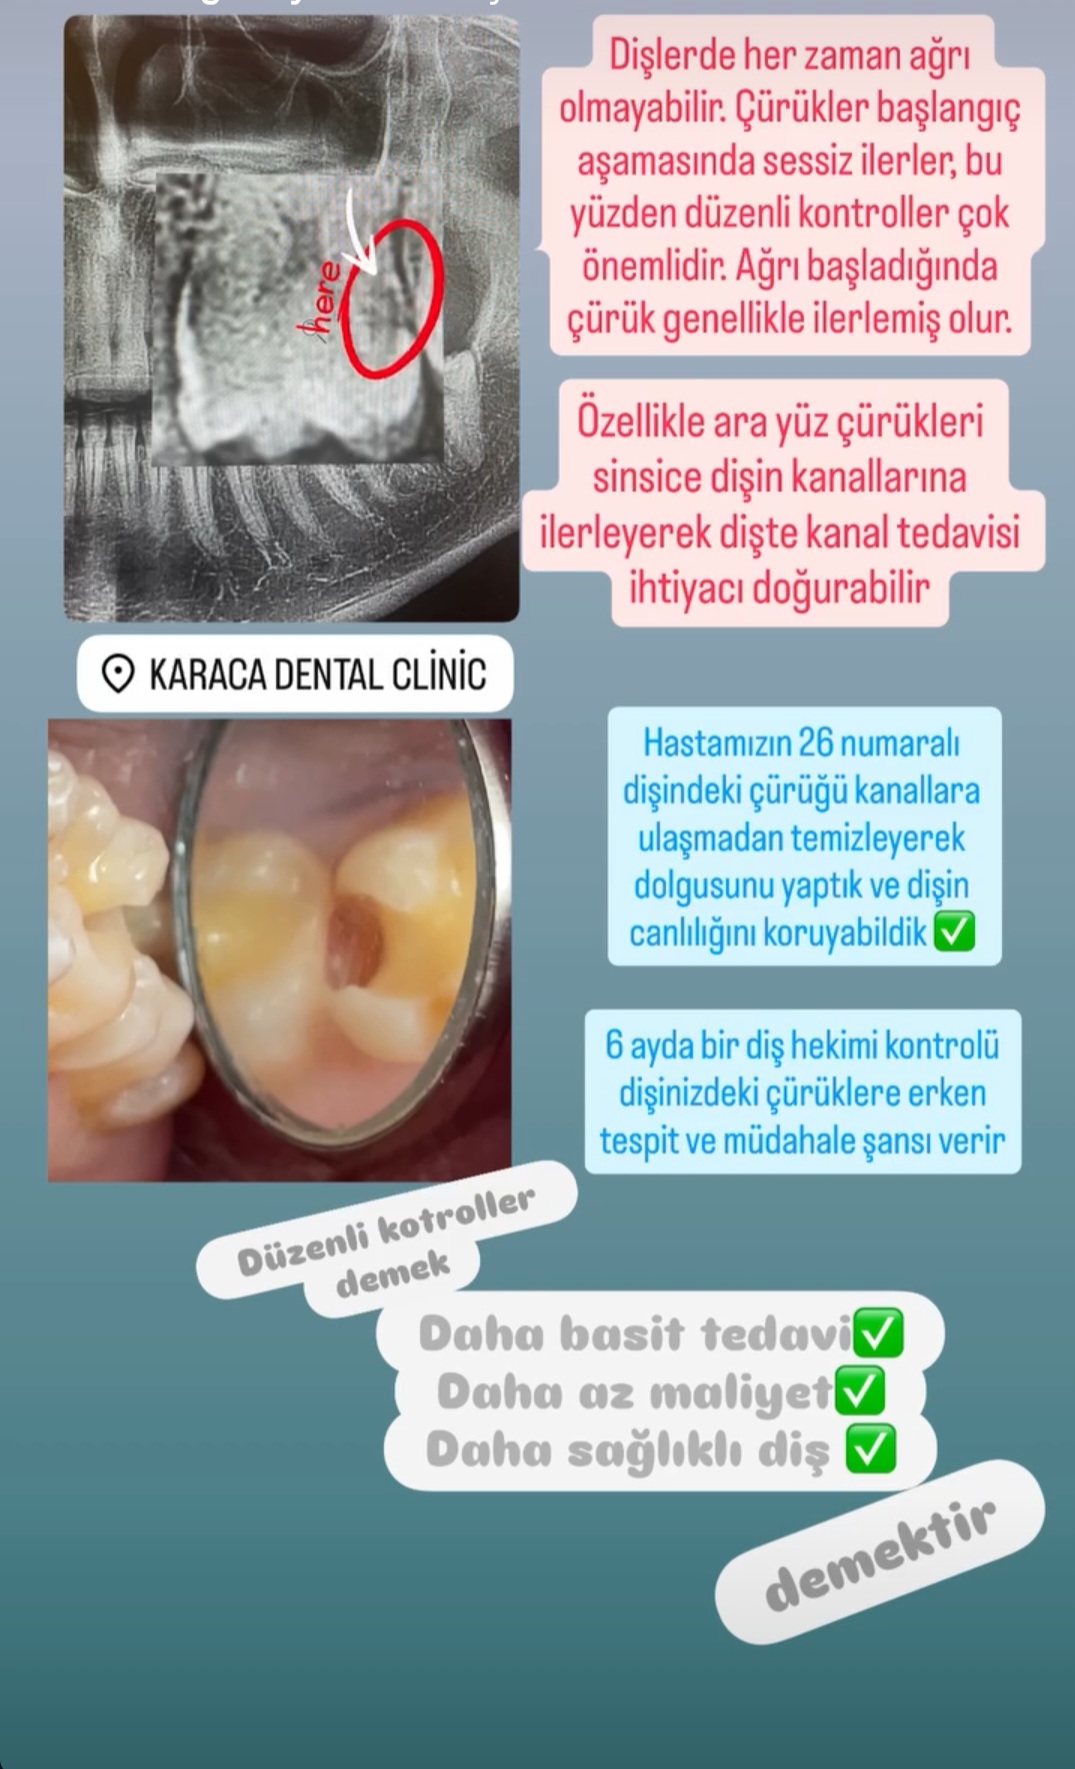

- Diş Dolgusu Kanal Tedavisi İmplant Tedavisi Çocuk Diş Hekimliği (Pedodonti) Lamina Kron Kaplama Zirkonyum Kron Kaplama Estetik Dolgu Estetik Gülüş Tasarımı Hollywood Gülüşü Diş Taşı Temizliği Air Flow Diş Temizleme Diş Beyazlatma Diş Çekimi Gece Plağı Dijital Diş Hekimliği 7/24 Diş Kliniği Hizmeti Acil Diş Kliniği Hizmeti Nöbetçi Diş Kliniği Hizmeti # HİZMETLERİMİZ #